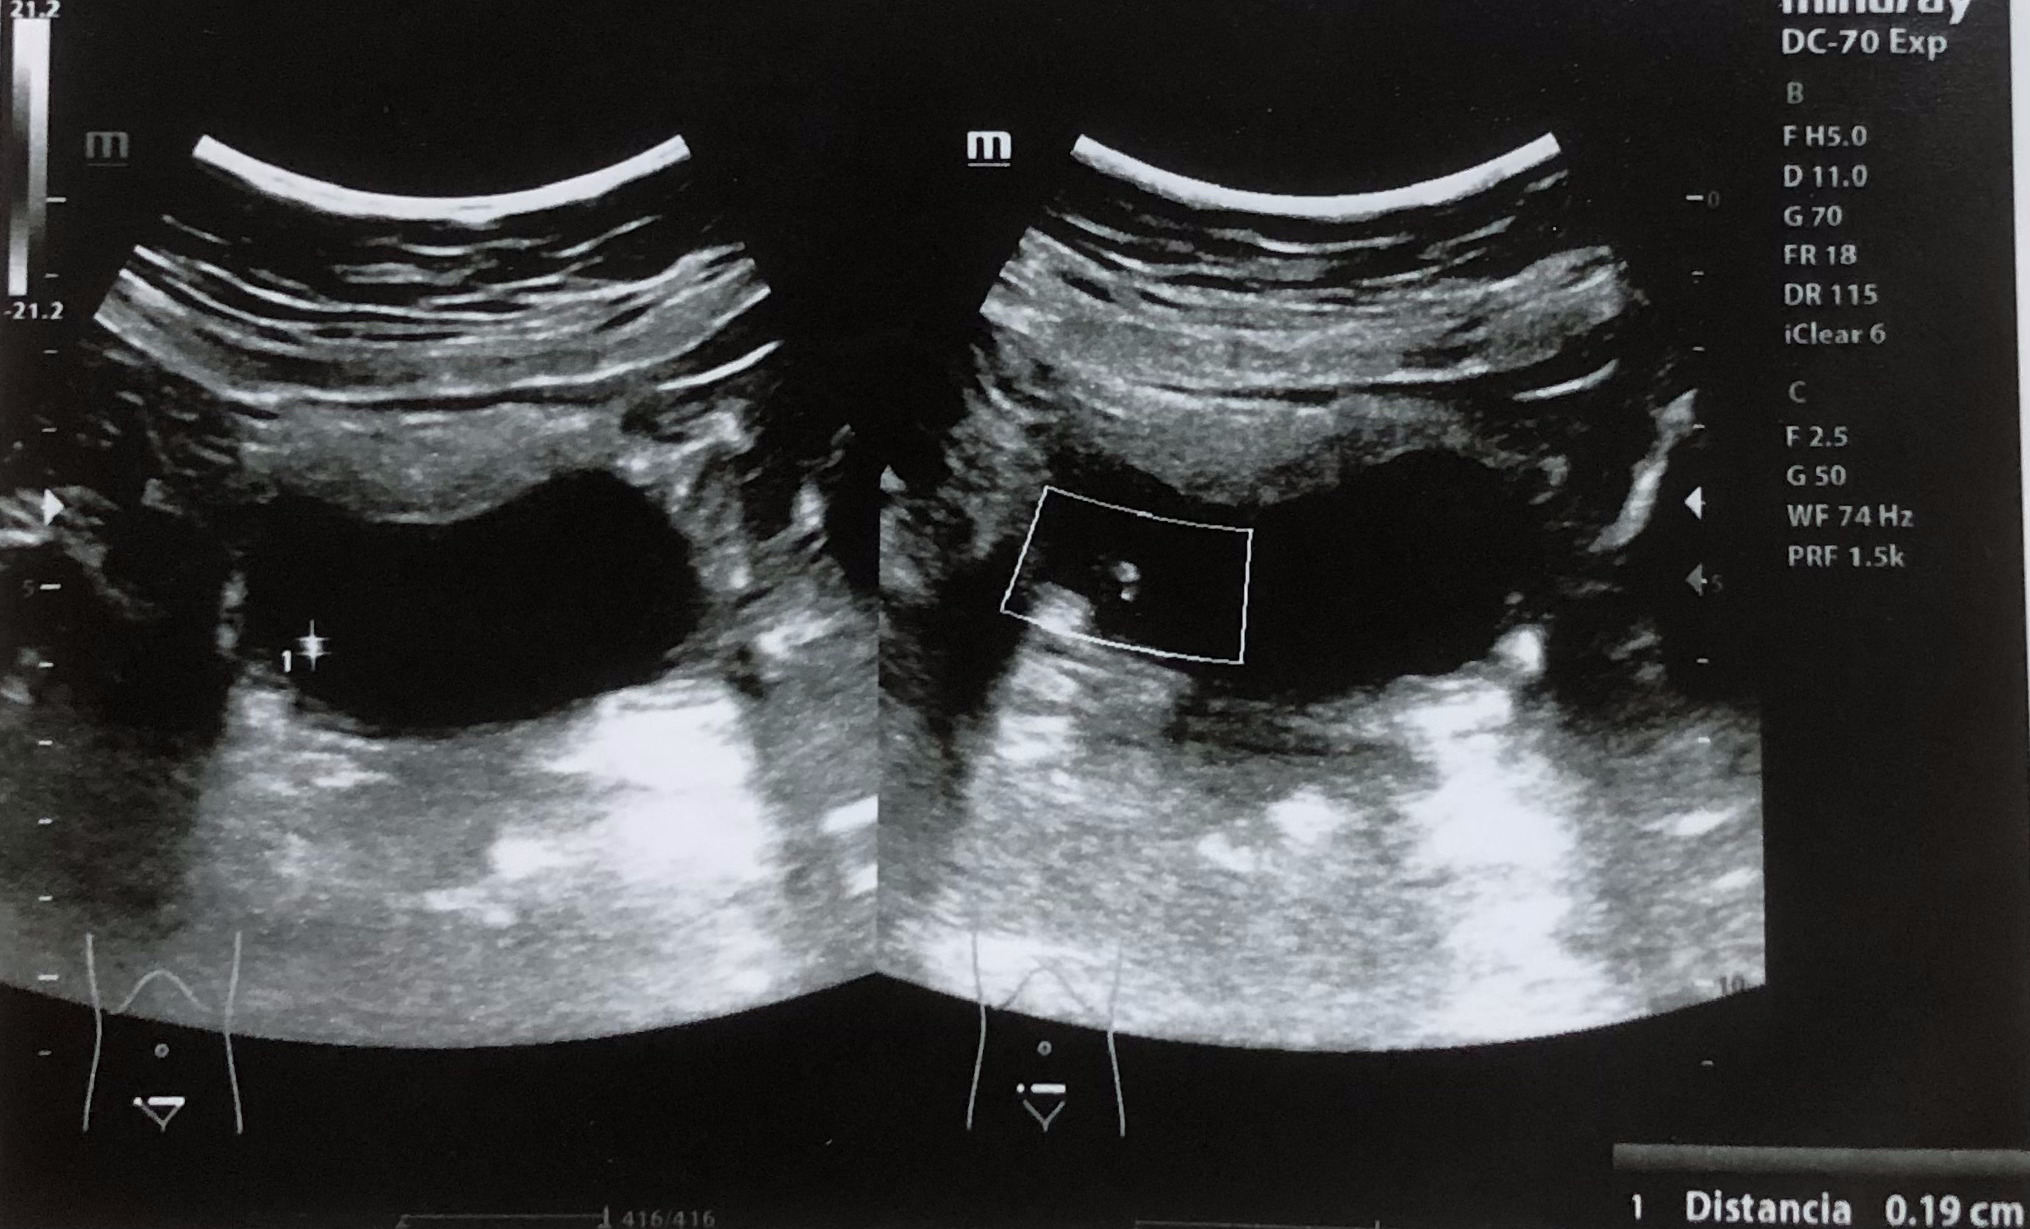

Se realiza ecografía renal donde se aprecia lesión hiperecogénica redondeada en pared inferior derecha de vejiga sin sombra posterior de 0,7 x 0,61 cm, que no se moviliza con cambios posturales de la paciente. Centelleo dudoso.

Dado tiempo de evolución y al continuar con dolor con uso reiterado de ibuprofeno se decide solicitar analítica con urianálisis y ecografía renal por la sospecha de litiasis renal complicada.

Como vemos la ecografía ayuda a una orientación diagnóstica ante signos de alarma y debemos utilizarla como una herramienta más en consulta. En este caso una paciente con dolor que no cede tras meses de evolución y abuso de antiinflamatorios, si bien realizamos la ecografía para descartar hidronefrosis u otra posible complicación de nefrolitiasis en ocasiones podemos encontrar lesiones potencialmente malignas.